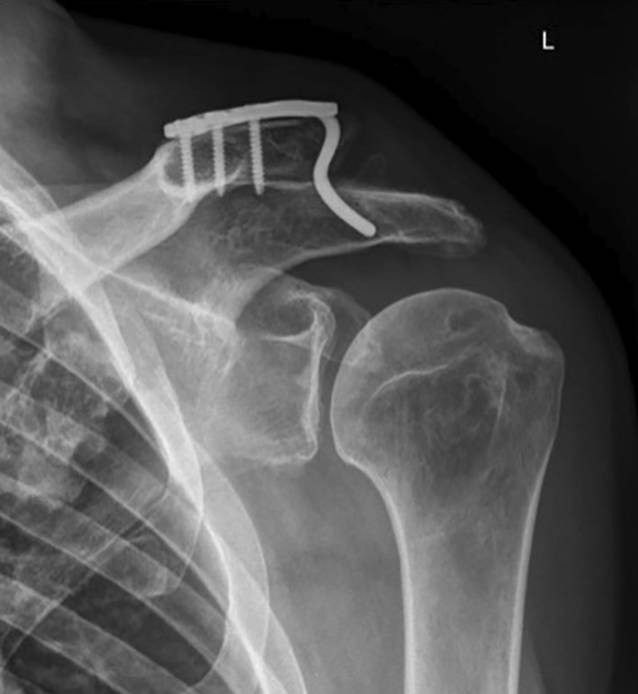

Das gezeigte Verfahren wird ergänzt durch eine Naht der Gelenkkapsel des AC-Gelenkes und einer Verstärkung der AC Kapsel durch ein zusätzliches Kunstband. AC Gelenk Folgen der Verletzung. Jedes Gelenk ist von einer Kapsel umhüllt.

Zusätzlich wird die Kapsel des AC Gelenkes genäht und häufig mit einem weiteren Kunstband verstärkt. Das Ende bildet das Schulterblatt. Kapsel Das Acromioclaviculargelenk ist ein echtes Gelenk Diarthrose mit schmalem Gelenkspalt.